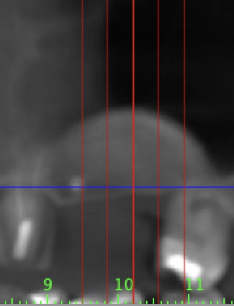

Implant placement after sinus lift with autologous and stratified allograft